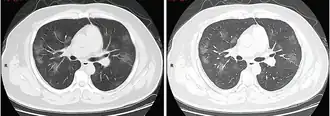

Tomografia computadorizada do tórax

Às vezes, tomografias computadorizadas (TC) do tórax podem ajudar a identificar e caracterizar o estado patológico pulmonar e produzir achados inespecíficos com a infecção por COVID-19. Um estudo descobriu que a sensibilidade da tomografia computadorizada para infecção por COVID-19 era de 98%, em comparação com a sensibilidade da RT-PCR de 71%. No entanto, o teste foi realizado em Wuhan, na China, e, por isso, pode não ser generalizado.[25][26] Grande parte dos achados consistia na presença de opacificação em vidro fosco na região subpleural e pavimentação em mosaico. Esses achados são inespecíficos, pois também são encontrados em outros tipos de pneumonia. Nenhum estudo avaliou, ainda, a precisão e o valor discriminatório das tomografias para distinguir a COVID de outras pneumonias virais.[27][28]